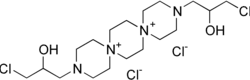

Prospidium chloride

1-Chloro-3-[12-(3-chloro-2-hydroxypropyl)-3,12-diaza-6,9-diazoniadispiro[5.2.59.26]hexadecan-3-yl]propan-2-ol dichloride

| C18H36Cl4N4O2 | |

| Molar mass | 482.31 g·mol−1 |

Prospidium chloride (prospidine) is a drug with cytostatic (alkylating) and anti-inflammatory properties. It has been studied for the treatment of rheumatoid arthritis.[1]